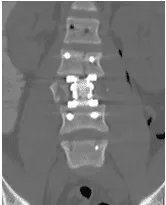

Patient was operated and the spinal canal cleaned up of all bony fragments. The spine was fixed from the side and the back to take care of instability.

Patient was sent to a rehab facility after the surgery and she made a quick and complete recovery in 5-6 months.